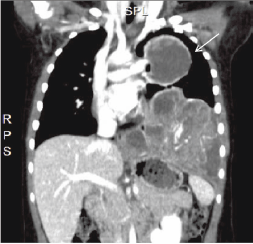

A four-year-old girl, without any medical history, was referred to our department for a lung mass (Figure 1). An initial thoracic computed tomography (CT) scan revealed a large cystic tumour in the middle of the left lung (Figure 2). The diagnosis of intrathoracic EES was made by punction under CT control. The patient was subsequently treated with six chemotherapy courses (vincristin, ifosfamid, doxorubicin, and etoposide).

Figure 1: CT scan: coronal reconstruction of a left lung mass (arrow)